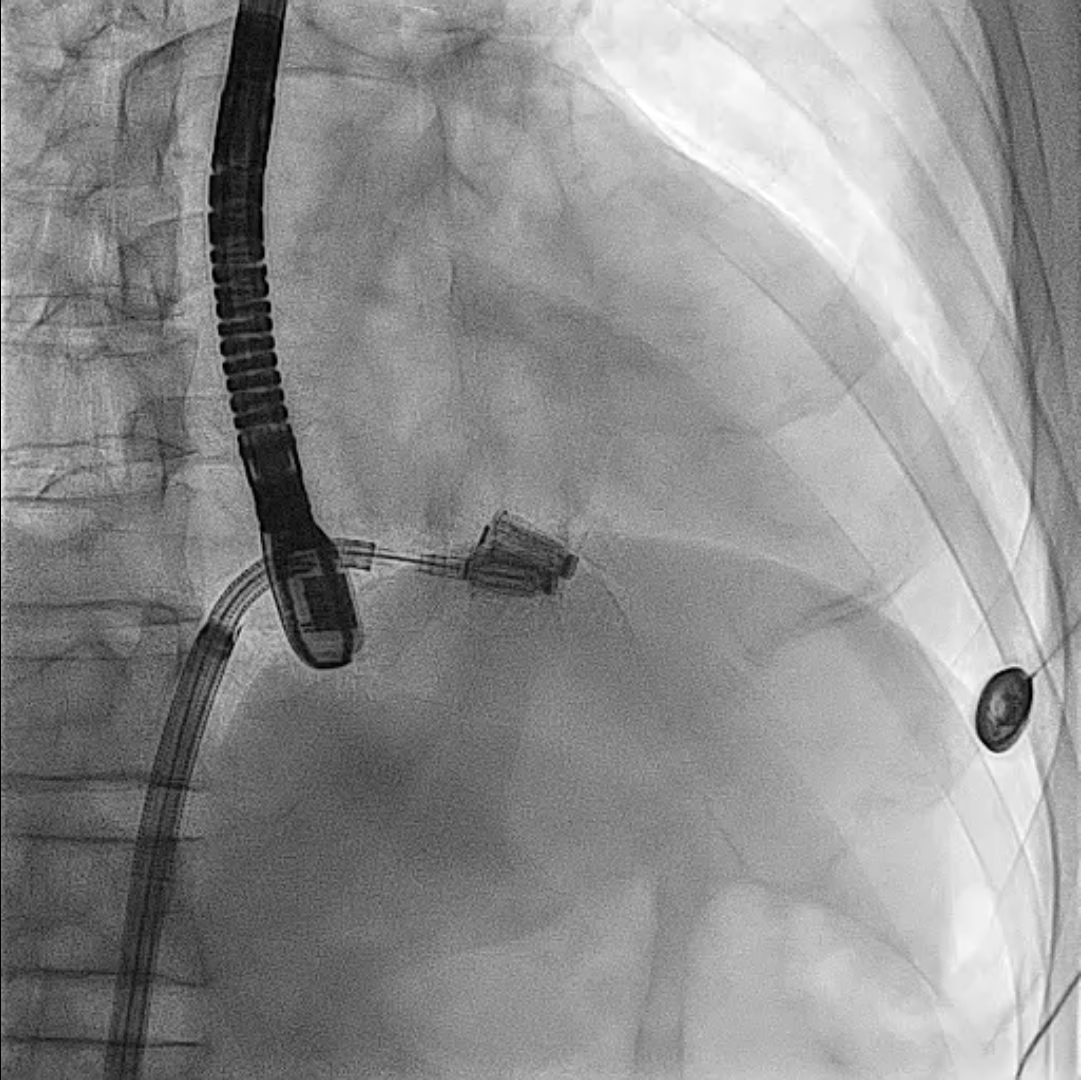

First, through the right femoral vein, the Neoblazar® delivery system (Dawneo Neoblazar, Hangzhou, China) was advanced till the tricuspid valve, and two clips (TMrCLAMP-S) were deployed to grasp the anterior and septal leaflets with a desired outcome reducing to a mild residual TR. Postoperative VC width was 0.2cm with EROA of 0.17cm2 and regurgitation volume of 15mL. The delivery system removed and 18 fr sheath exchanged. A 5 fr temporary pacemaker wire positioned through sheath into the right ventricle. Subsequently, the right and left femoral arteries were each accessed with 6-fr sheath and 22 fr sheath respectively. Through the left femoral artery, the TAVI delivery system with a 30mm VitaFlow Liberty™ self-expanding valve system (MicroPort®, Shanghai, China) was advanced across the aortic valve and deployed under transoesophageal and fluoroscopic guidance with rapid ventricular pacing at 140 beats/minute and pacing slowly tapered. The mean valvular gradient after TAVI decreased to 6 mmHg. Then, percutaneous access closure of arterial access was achieved using a pre-closure technique with the suture-mediated ProGlide device (Abbott Laboratories Inc., Chicago, Illinois, United States). The total procedure time was 60min. There were no intraoperative complications. The temporary pacemaker was removed two days later. Predischarge transthoracic echocardiogram showed a normal functioning aortic THV with a mean gradient of 6mmHg and mild residual tricuspid regurgitation.